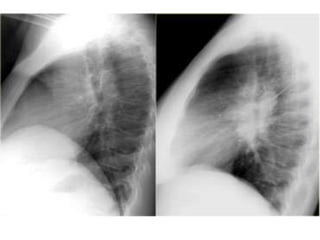

Upper lobe consolidation

Middle and Lower lobe consolidation

Left lower lobe consolidation